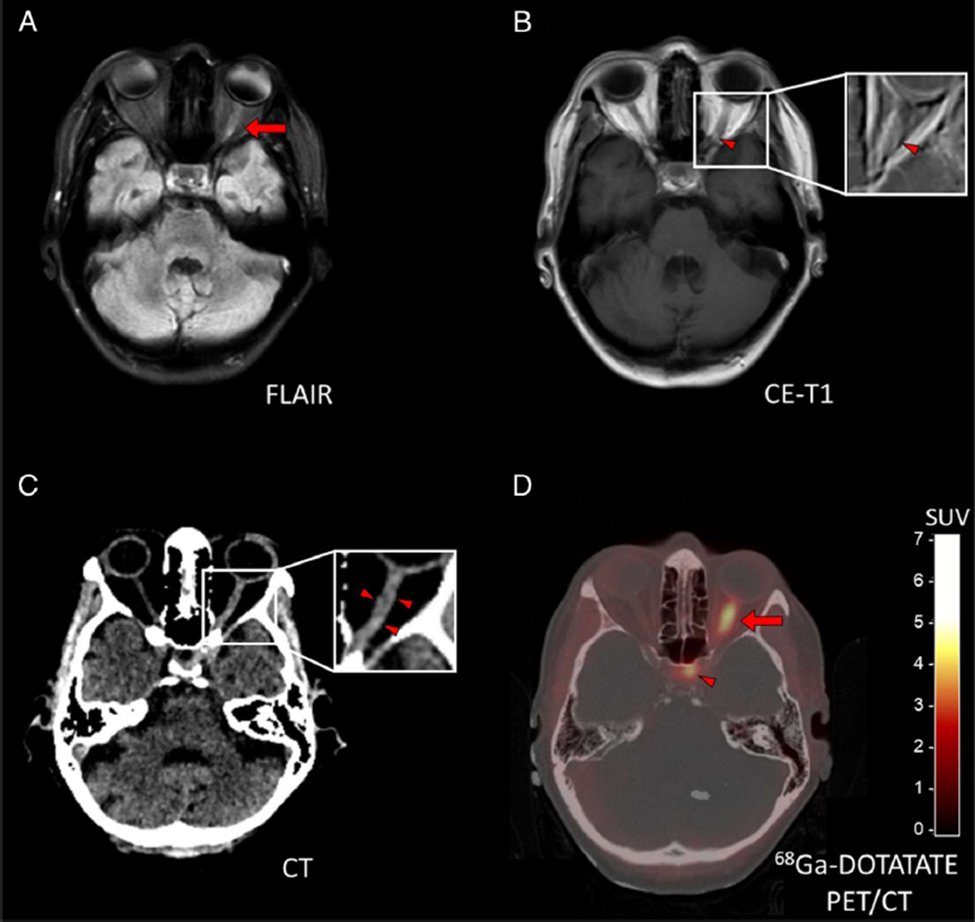

Can DOTATATE-Pet help diagnose Optic nerve sheath meningioma? YES according to these studies 56 yo initially diagnosed optic neuritis, yet older age, no MS, neg oligoclonal bands, prog ���↓ vision on steroids. DOTATATE helpful w/ diagnosis ONSM https://t.co/mhsVFv0xLh